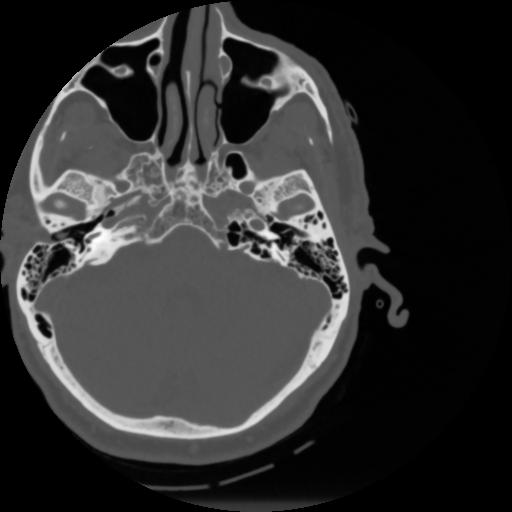

4 CEREBRO,,Vol,0.5,CEREBRO,,